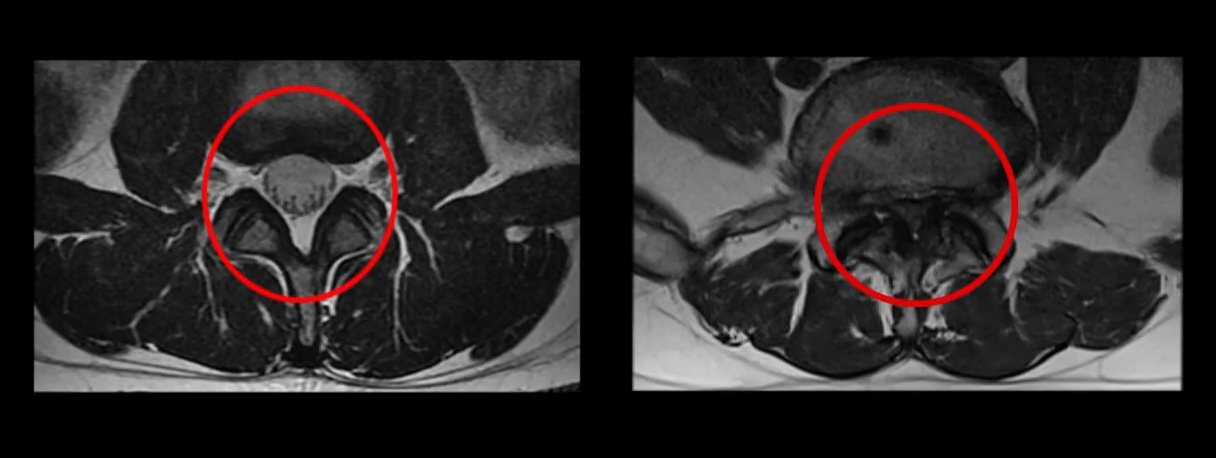

여기 MRI 화면을 보고 설명 드리겠습니다. 척추관협착증 환자의 MRI입니다. 척추를 이렇게 잘라서 보는 겁니다. 왼쪽의 정상적인 척추관에 비해 오른쪽의 협착이 있는 척추관은 척추뼈, 척추후관절, 인대, 디스크 등 척추구조물들의 퇴행성 변화로 인해 척추 신경다발이 지나가는 통로인 척추관이 좁아지면서 신경다발이 전체적으로 눌려 있는 모습입니다.

추간공협착증 환자의 MRI입니다. 척추를 이렇게 옆으로 잘라서 보는 겁니다. 척추 신경다발에서 갈라져 빠져 나온 신경가지 하나가 지나가는 구멍을 추간공이라고 하는데 여기 보이시는 것처럼 이 추간공이 좁아져 신경가지 하나가 눌려 있는 모습입니다.